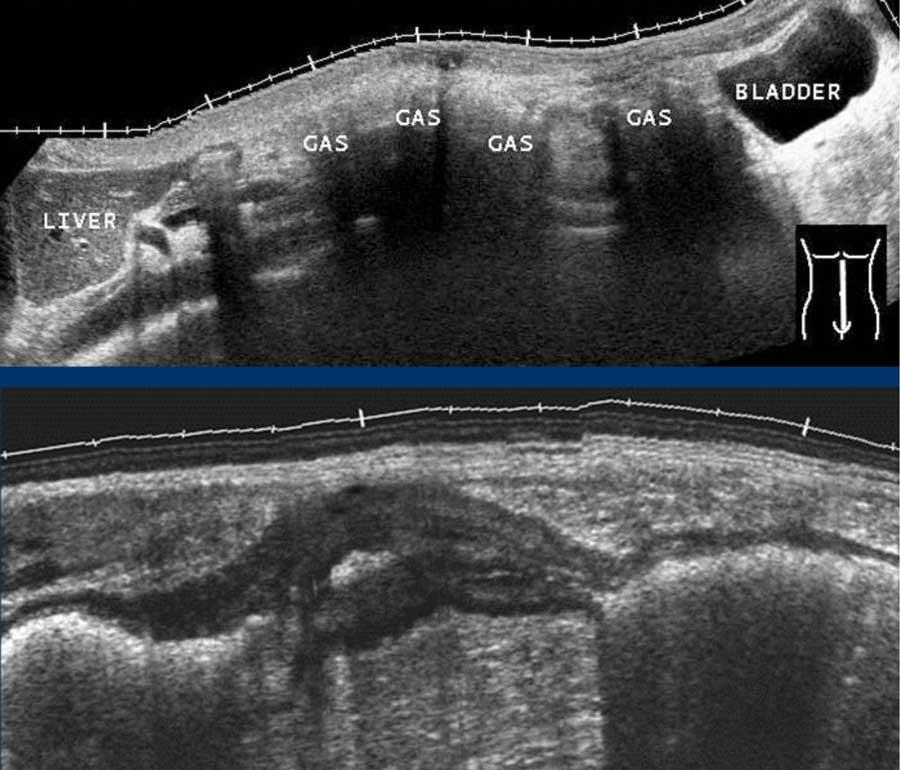

Siêu âm đường tiêu hóa trước đây khá ít được ưa chuộng do sự cản trở của hơi và các thành phần khác trong lòng ruột (hình trên).

Tin tốt là ruột bệnh lý thường dễ nhận thấy do thành ruột dày khu trú và lòng ruột rỗng, ví dụ như ở bệnh nhân này với viêm đại tràng Crohn từng đoạn (hình dưới).